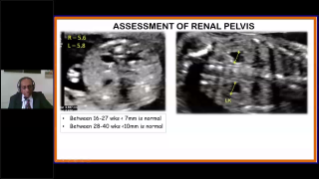

Using ultrasound as part of an optimised OBG workflow can support large patient volumes for women's health screening. For example, central nervous system (CNS) malformations are one of the most common congenital abnormalities. Due to imaging conditions such as poor fetal position, the median sagittal plane (MSP) is particularly difficult to obtain from 2D ultrasound. Therefore, automated detection and measurements can greatly enhance scanning efficiency.